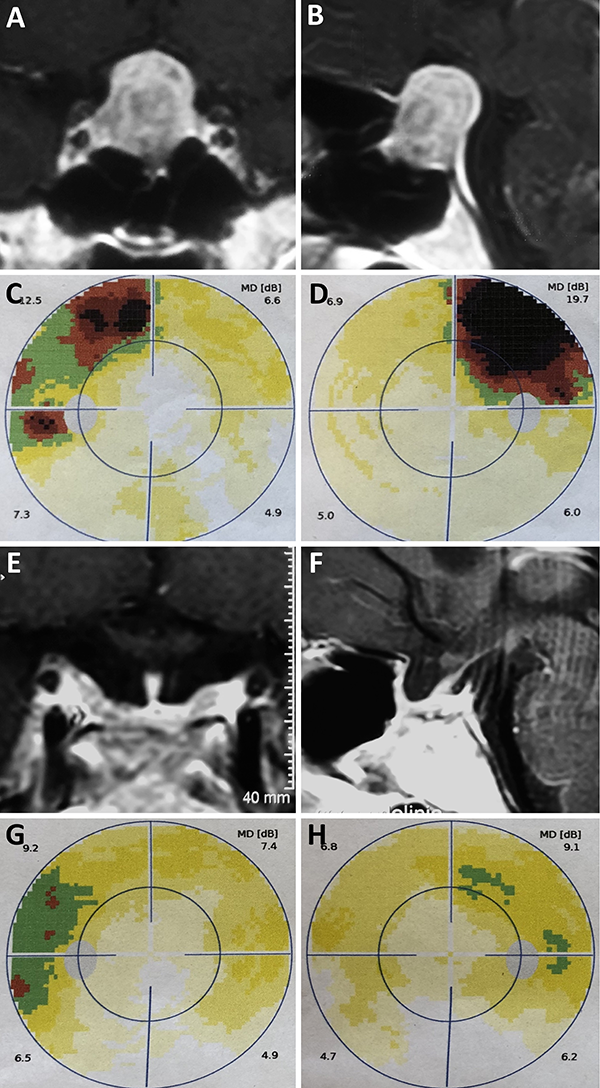

Una clasificación clásica de los adenomas es según su tamaño. Se los clasifica en microadenoma <10 mm (fig. 2), macroadenoma >10 mm (fig. 3), y adenoma gigante > 30 mm (fig. 4). Esta clasificación es importante ya que los índices de remisión están ligados al tamaño del adenoma y también su recidiva.12

Figura 3: Macroadenoma. A-B: RM preoperatoria; C-D: Campo visual preoperatorio; E-F: RM postoperatoria; G-H: Campo visual postoperatorio.